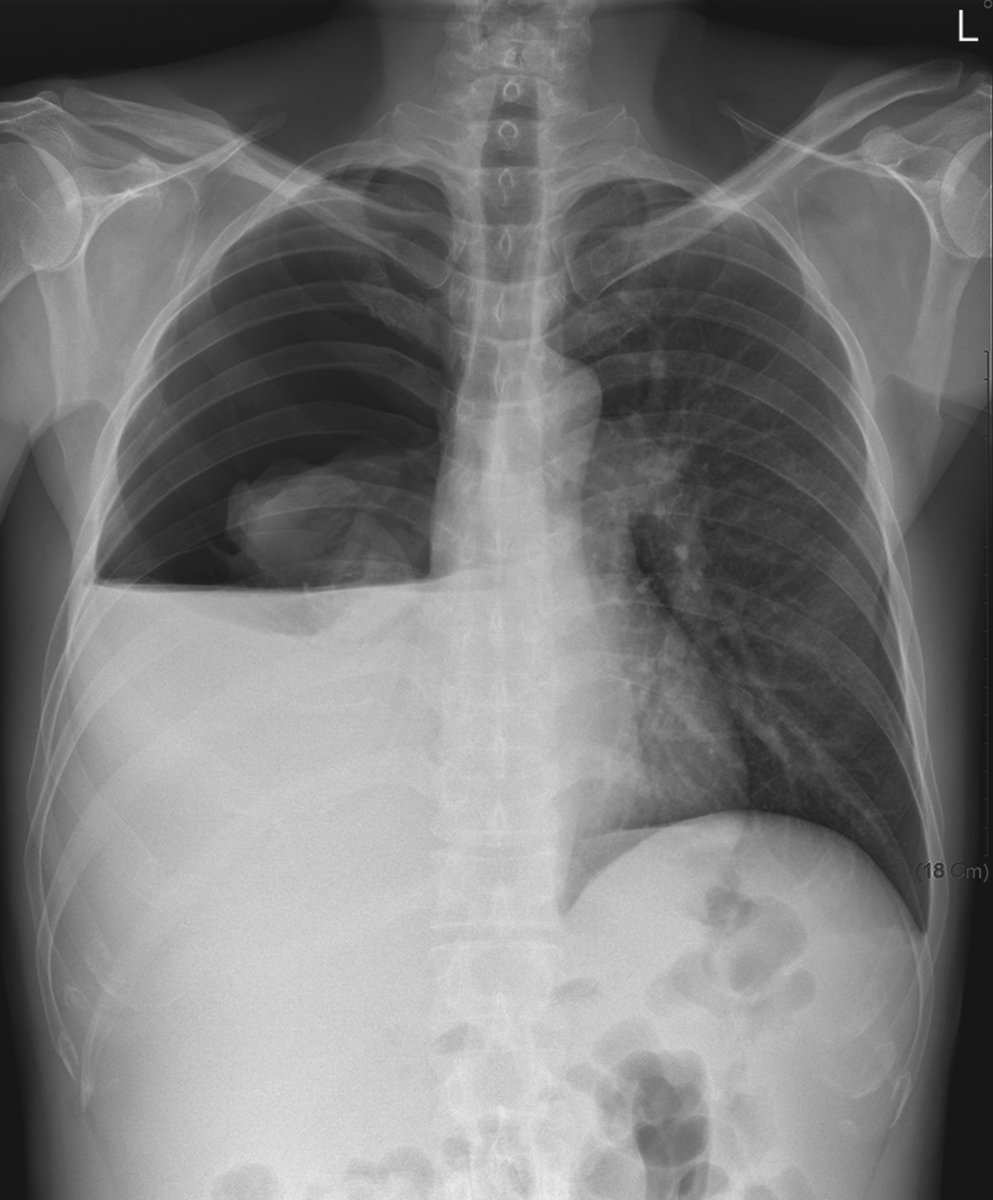

We have published from the @LaheyHospital lung cancer screening program a 0.95% invasive procedure (Dx or Tx) rate in patients without cancer with 0.36% grade III or higher complication rate.

Lung Cancer Screening is SAFE!